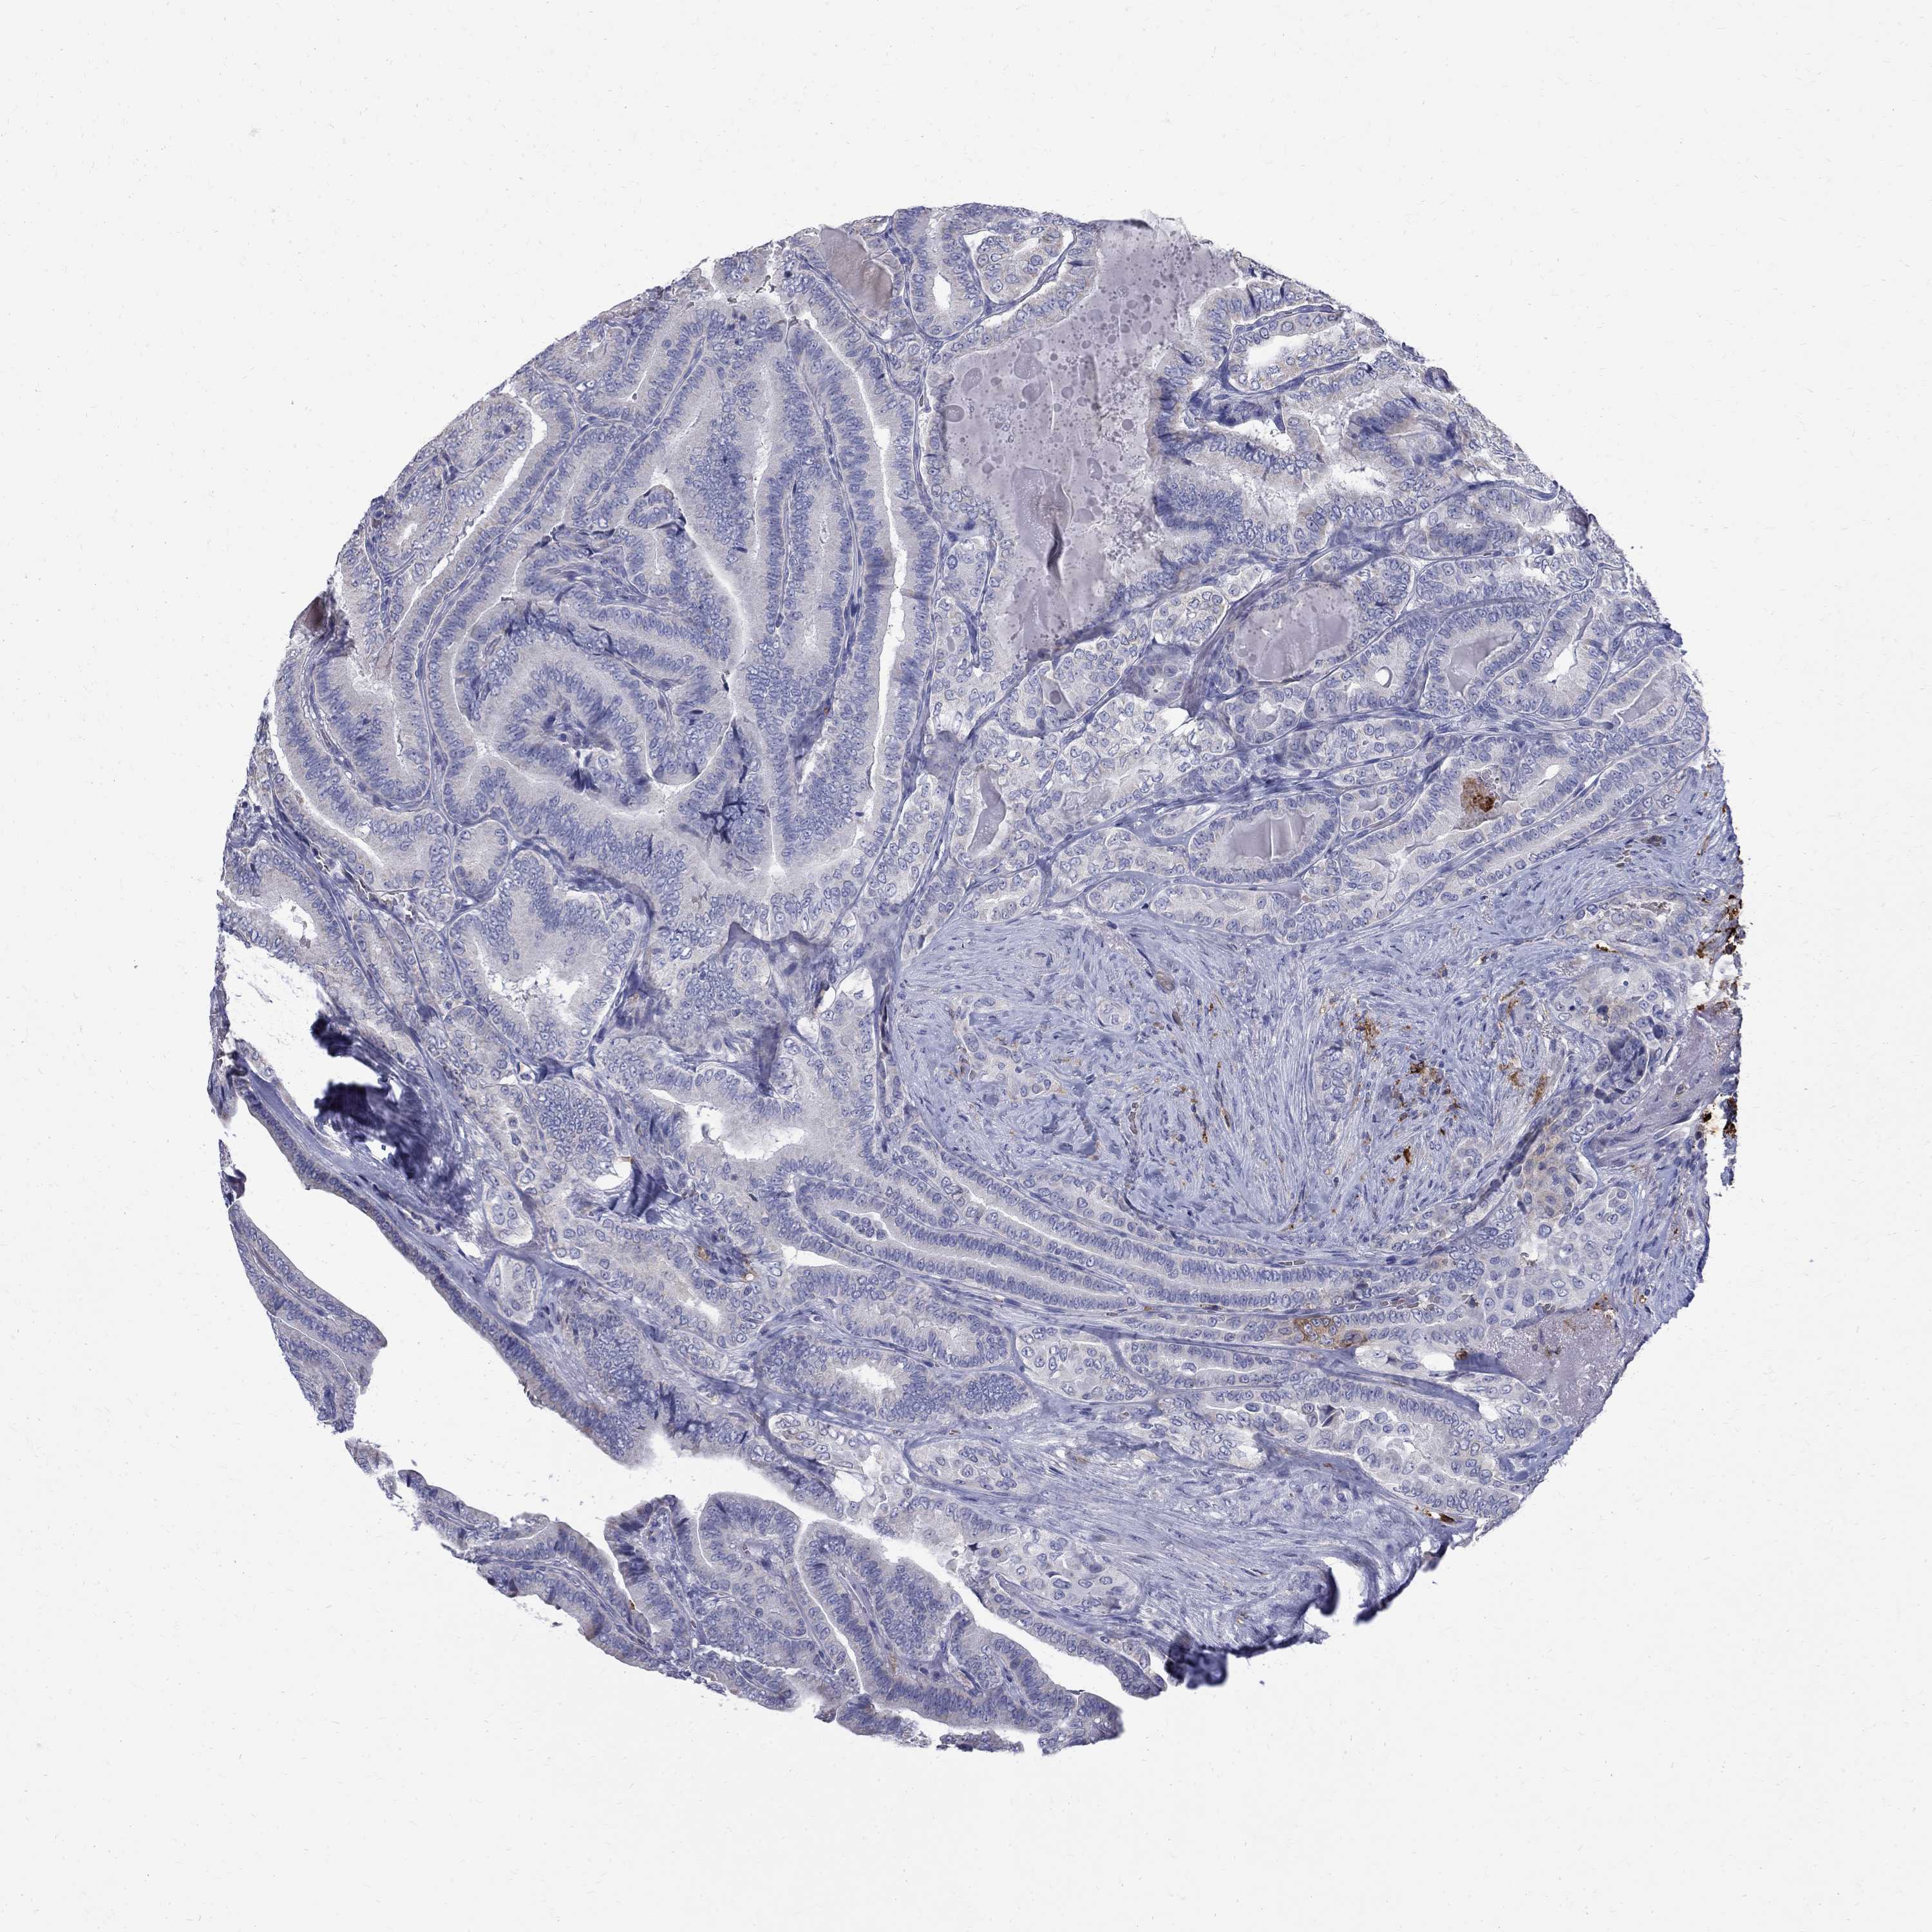

THYROID CANCER - Protein expressioni

A mouse-over function shows sample information and annotation data. Click on an image to view it in a full screen mode. Samples can be filtered based on level of antibody staining by selecting one or several of the following categories: high, medium, low and not detected. The assay and annotation is described here.

Note that samples used for immunohistochemistry by the Human Protein Atlas do not correspond to samples in the TCGA dataset.

Antibody stainingi

Antibody staining in the annotated cell types in the current human tissue is reported as not detected, low, medium, or high, based on conventional immunohistochemistry profiling in selected tissues. This score is based on the combination of the staining intensity and fraction of stained cells.

Each image is clickable and will lead to virtual microscopy that enables deeper exploration of all samples and also displays staining intensity scores, fraction scores and subcellular localization as well as patient and tissue information for each sample.

Antibody HPA069474

Antibody CAB011682

Staining

High

Medium

Low

Not detected

Intensity

Strong

Moderate

Weak

Negative

Quantity

>75%

75%-25%

<25%

None

Location

Nuclear

Cytoplasmic/membranous

Cytoplasmic/membranous,nuclear

Papillary adenocarcinoma, NOS

Follicular adenoma carcinoma, NOS